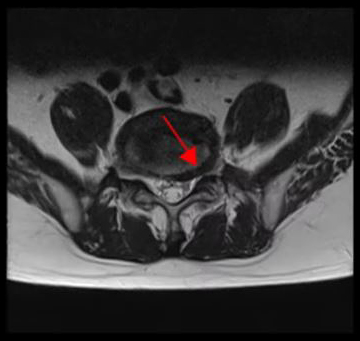

<4-5번 추간공협착증>

<4-5번 척추전방전위증>

<5-1번 디스크 파열>

이 환자분의 허리 MRI를 보면 4번, 5번 오른쪽에 심한 추간공협착증과 2단계의 척추전방전위증이 있는데, 특히 척추전방전위증 때문에 추간공이 많이 좁아져 있는 상태입니다. 또 왼쪽의 다른 마디에 디스크 파열이 있으나 환자분이 왼쪽으로는 증상이 전혀 없는 것으로 보아 이 디스크 파열은 통증을 일으키지 않는 무증상의 디스크 파열입니다.

이렇듯 4번, 5번 마디의 심한 추간공협착증과 척추전방전위증으로 인해 이 환자분은 다리에 마비가 왔고, 발목에 힘이 빠져 거의 걷지 못하는 상태였습니다. 새벽에 잠에서 깨 화장실을 갈 때는 네 발로 기어갈 정도로 증상이 심했습니다. 신경주사도 많이 맞아봤지만 통증이 전혀 줄지 않아서 결국 수술을 결심하셨는데요. 대학병원을 비롯해 정형외과 및 신경외과 등 아홉 군데 병원에서 진료를 받았지만, 어려운 수술이라고 말하면서 척추유합술, 감압술 등 병원마다 제시하는 수술방법이 다 달라 큰 혼란을 겪으셨습니다. 게다가 수술 후 후유증이나 잔존 증상에 대한 물음에 ‘있을 수도 있고 없을 수도 있다’라는 의사의 말에 수술을 고민하던 중 마지막이라는 생각으로 저희 모커리에 내원하셨습니다.